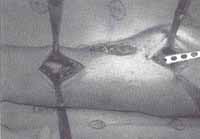

Liberación del torniquete, hemostasia, lavado del área quirúrgica, cierre de las heridas quirúrgicas, y cierre primario tardío de lesiones si es posible (figura 5).

Figura 5